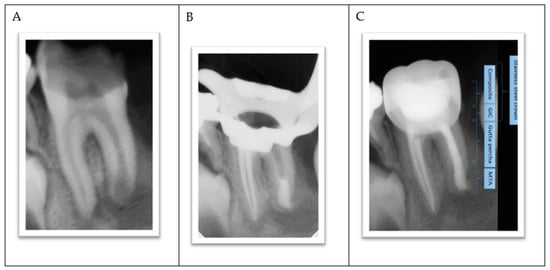

- The procedure involved local anesthesia and rubber dam isolation.

- A pinpoint pulp exposure happened (Figure 6A).

- A coronal pulpotomy was completed by removal of coronal pulp tissue.

- Hemostasis was achieved using 5% sodium hypochlorite and MTA placed as a dressing material over pulp orifices (Figure 6B).

- The tooth was restored like teeth #36 and #46.